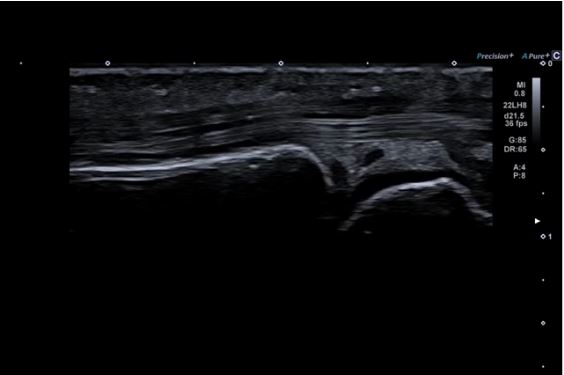

iBeam+

Особливі технології обробки зображень Aplio можуть допомогти покращити якість зображення шляхом зменшення шумів, посилення сигналу та покращення візуалізації.

Система обробки зображень iBeam+ використовує вдосконалену обробку сигналів для більш точного й гнучкого керування ультразвуковими променями, що робить зображення більш глибоким і чітким.